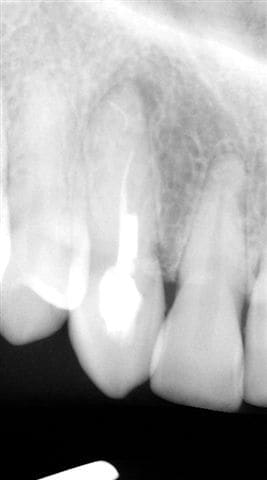

-La seule "nouvelle" technologie qui semble enfin acceptée par le plus grand nombre d'entre nous est l'implantologie, à tel point que des abus sont faits, à savoir extractions intempestives de certaines dents tout à fait conservables grâce à la paro ou l'endo cf radios ci-joint, la dernière ayant été faite un an après le traitement ("madame, votre canine est infectée de façon très importante, on ne peut pas la sauvée, nous allons l'extraire et poser un implant"...)

016 iz9c3d - Eugenol

021 qxjakd - Eugenol

004 s729bo - Eugenol